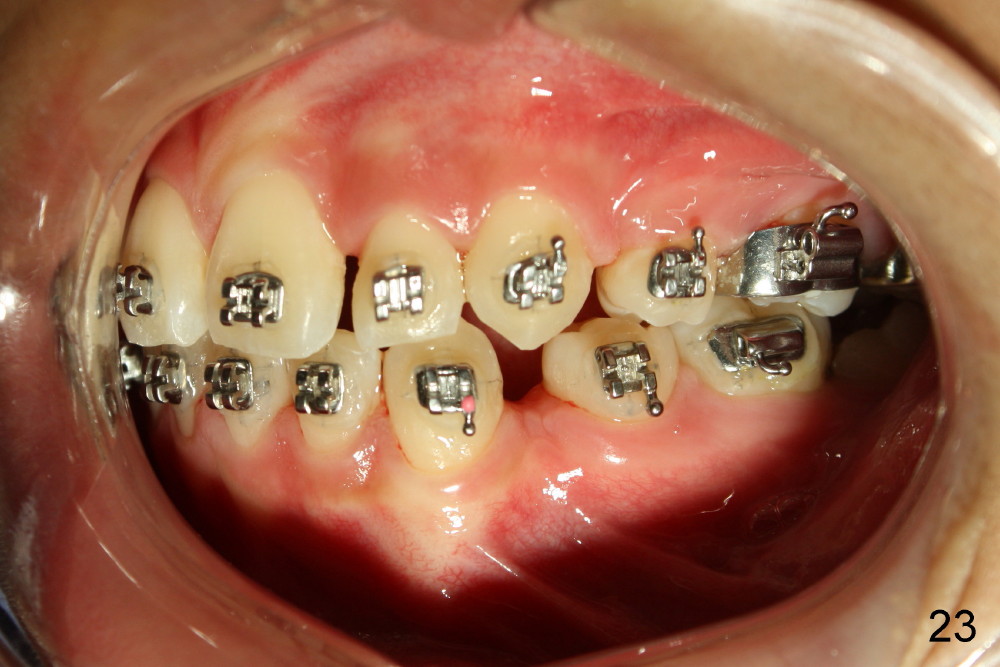

A 13-year-old boy has severe crowding (Fig.1-5). Four of the first bicuspids were extracted on 02/17/2014. Full mouth brackets or bands (except #18) were placed on 03/27/2014. Alignment improved 2 months later (Fig.11, 05/24/2014). The upper 18 ss wire was modified (Fig.12), and fixed with alastiks (Fig.13,14). One month later (07/01/2014), local alignment also improved (Fig.15); the upper modification is confined to one tooth.

Four and a half months post bracketing (Fig.21-25), what do you find and what should be done next?